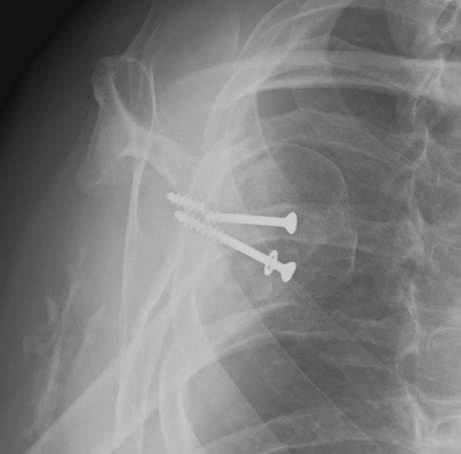

Complete bony union of Latarjet

Nonunion / fibrous union

Hardware issues

Screw backout

Intra-articular screw

Graft malposition

Screws and graft too medial

Bone graft too medial

Coracoid graft too superior on glenoid

Osteoarthritis

Nonunion with failure of fixation / recurrent instability

Nonunion with failure of fixation

Latarjet nonunion with hardware failure and displacement of coracoid fragment